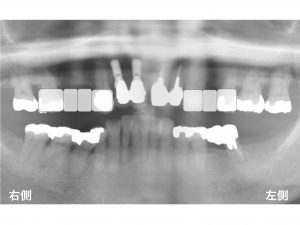

以下は初診時です。

上顎の右側に2歯欠損、

上顎の左側に1歯欠損があります。

上顎の前歯部には、

すでにインプラント治療がされている状態での来院でした。